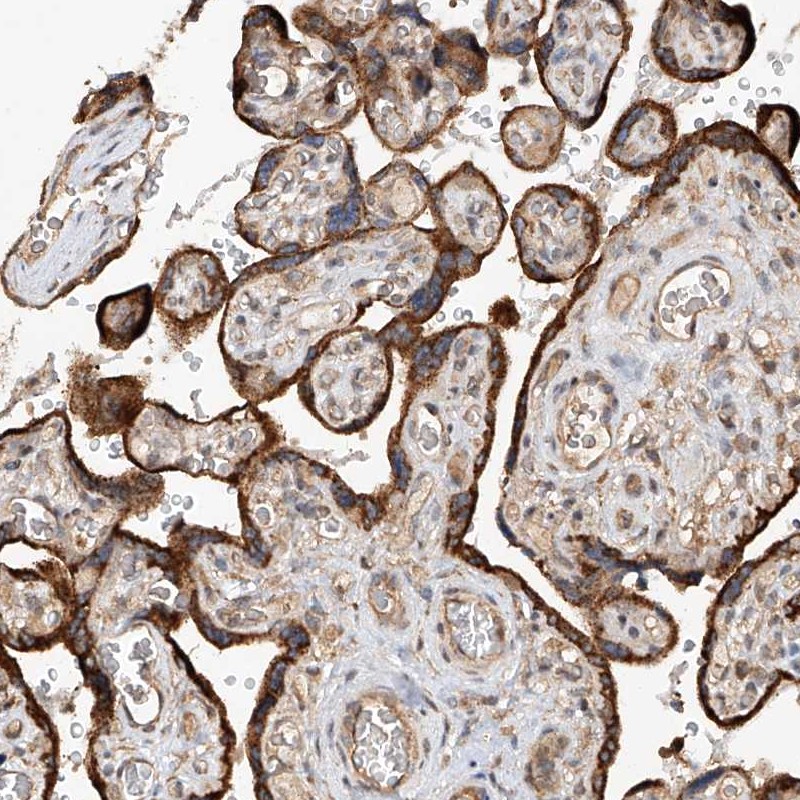

Immunohistochemical staining of human placenta shows strong cytoplasmic positivity in trophoblastic cells.